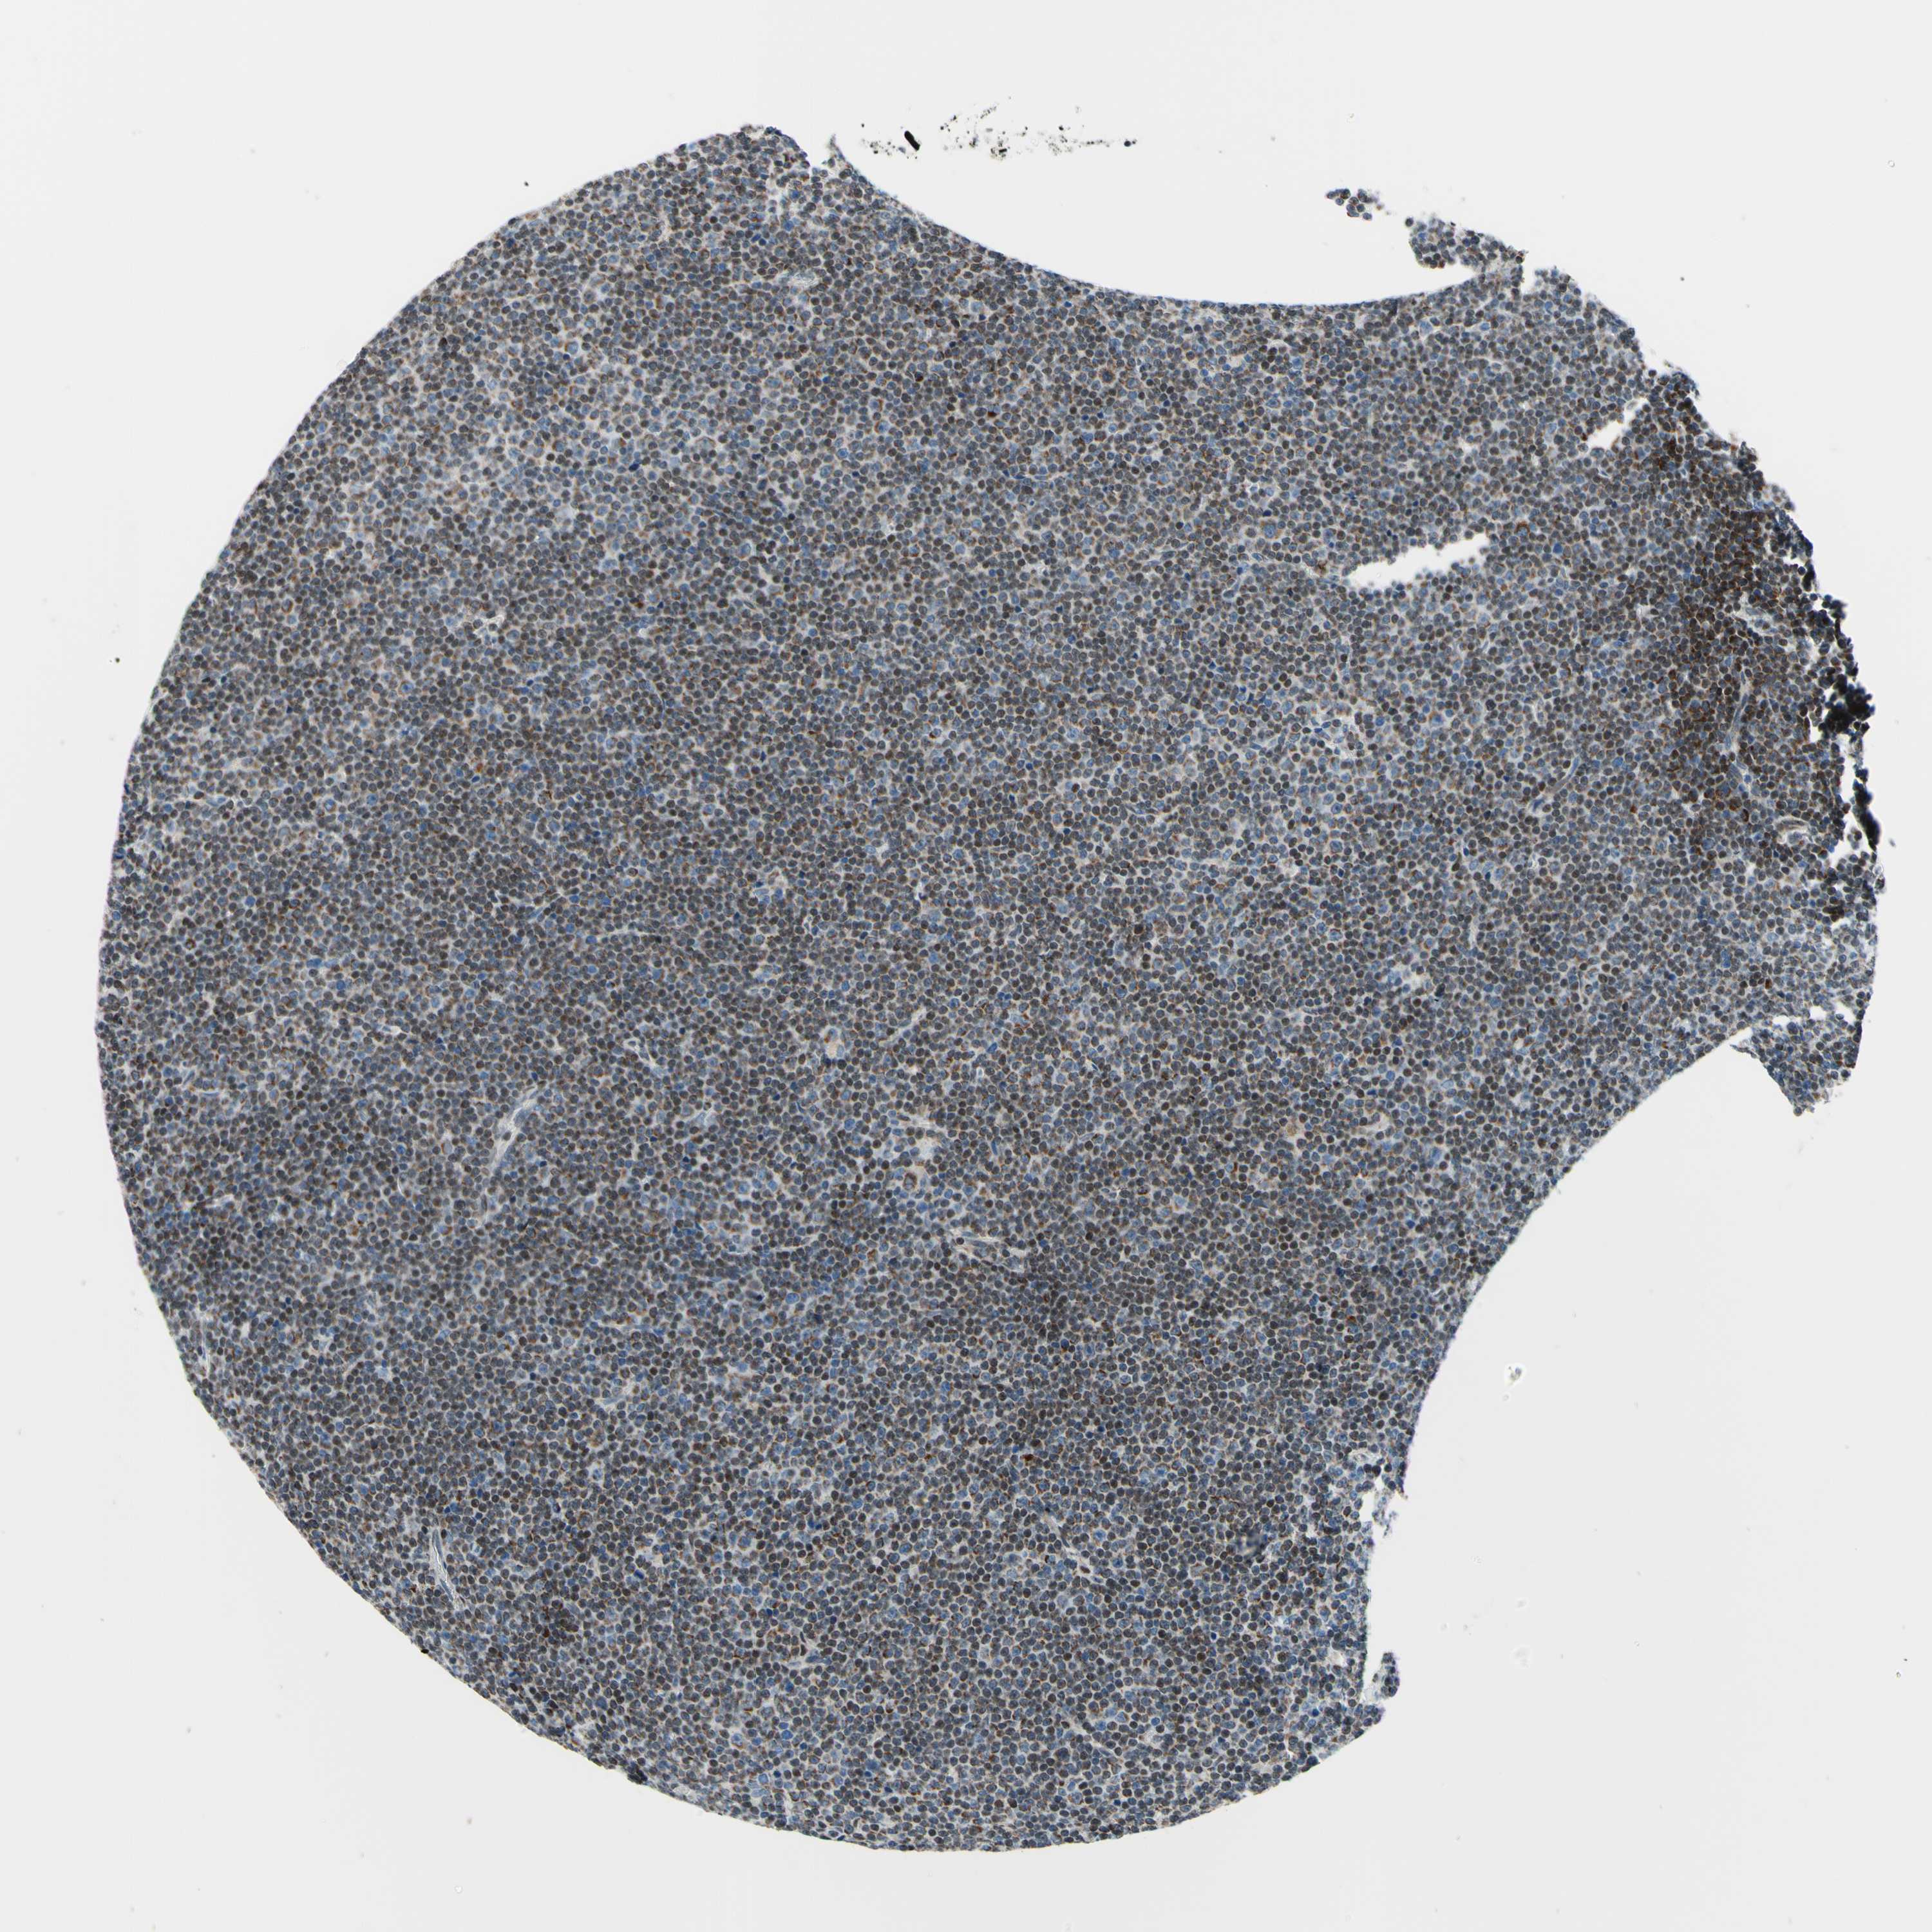

CANCER LYMPHOMA Show tissue menu

LYMPHOMA - Protein expressioni

A mouse-over function shows sample information and annotation data. Click on an image to view it in a full screen mode. Samples can be filtered based on level of antibody staining by selecting one or several of the following categories: high, medium, low and not detected. The assay and annotation is described here.

Each image is clickable and will lead to virtual microscopy that enables deeper exploration of all samples and also displays staining intensity scores, fraction scores and subcellular localization as well as patient and tissue information for each sample.

Antibody HPA048677

Antibody HPA056480

Antibody CAB011574

Staining

High

Medium

Low

Not detected

Intensity

Strong

Moderate

Weak

Negative

Quantity

>75%

75%-25%

<25%

None

Location

Nuclear

Cytoplasmic/membranous

Cytoplasmic/membranous,nuclear

Hodgkin's disease, NOS

Malignant lymphoma, non-Hodgkin's type, High grade

Malignant lymphoma, non-Hodgkin's type, Low grade